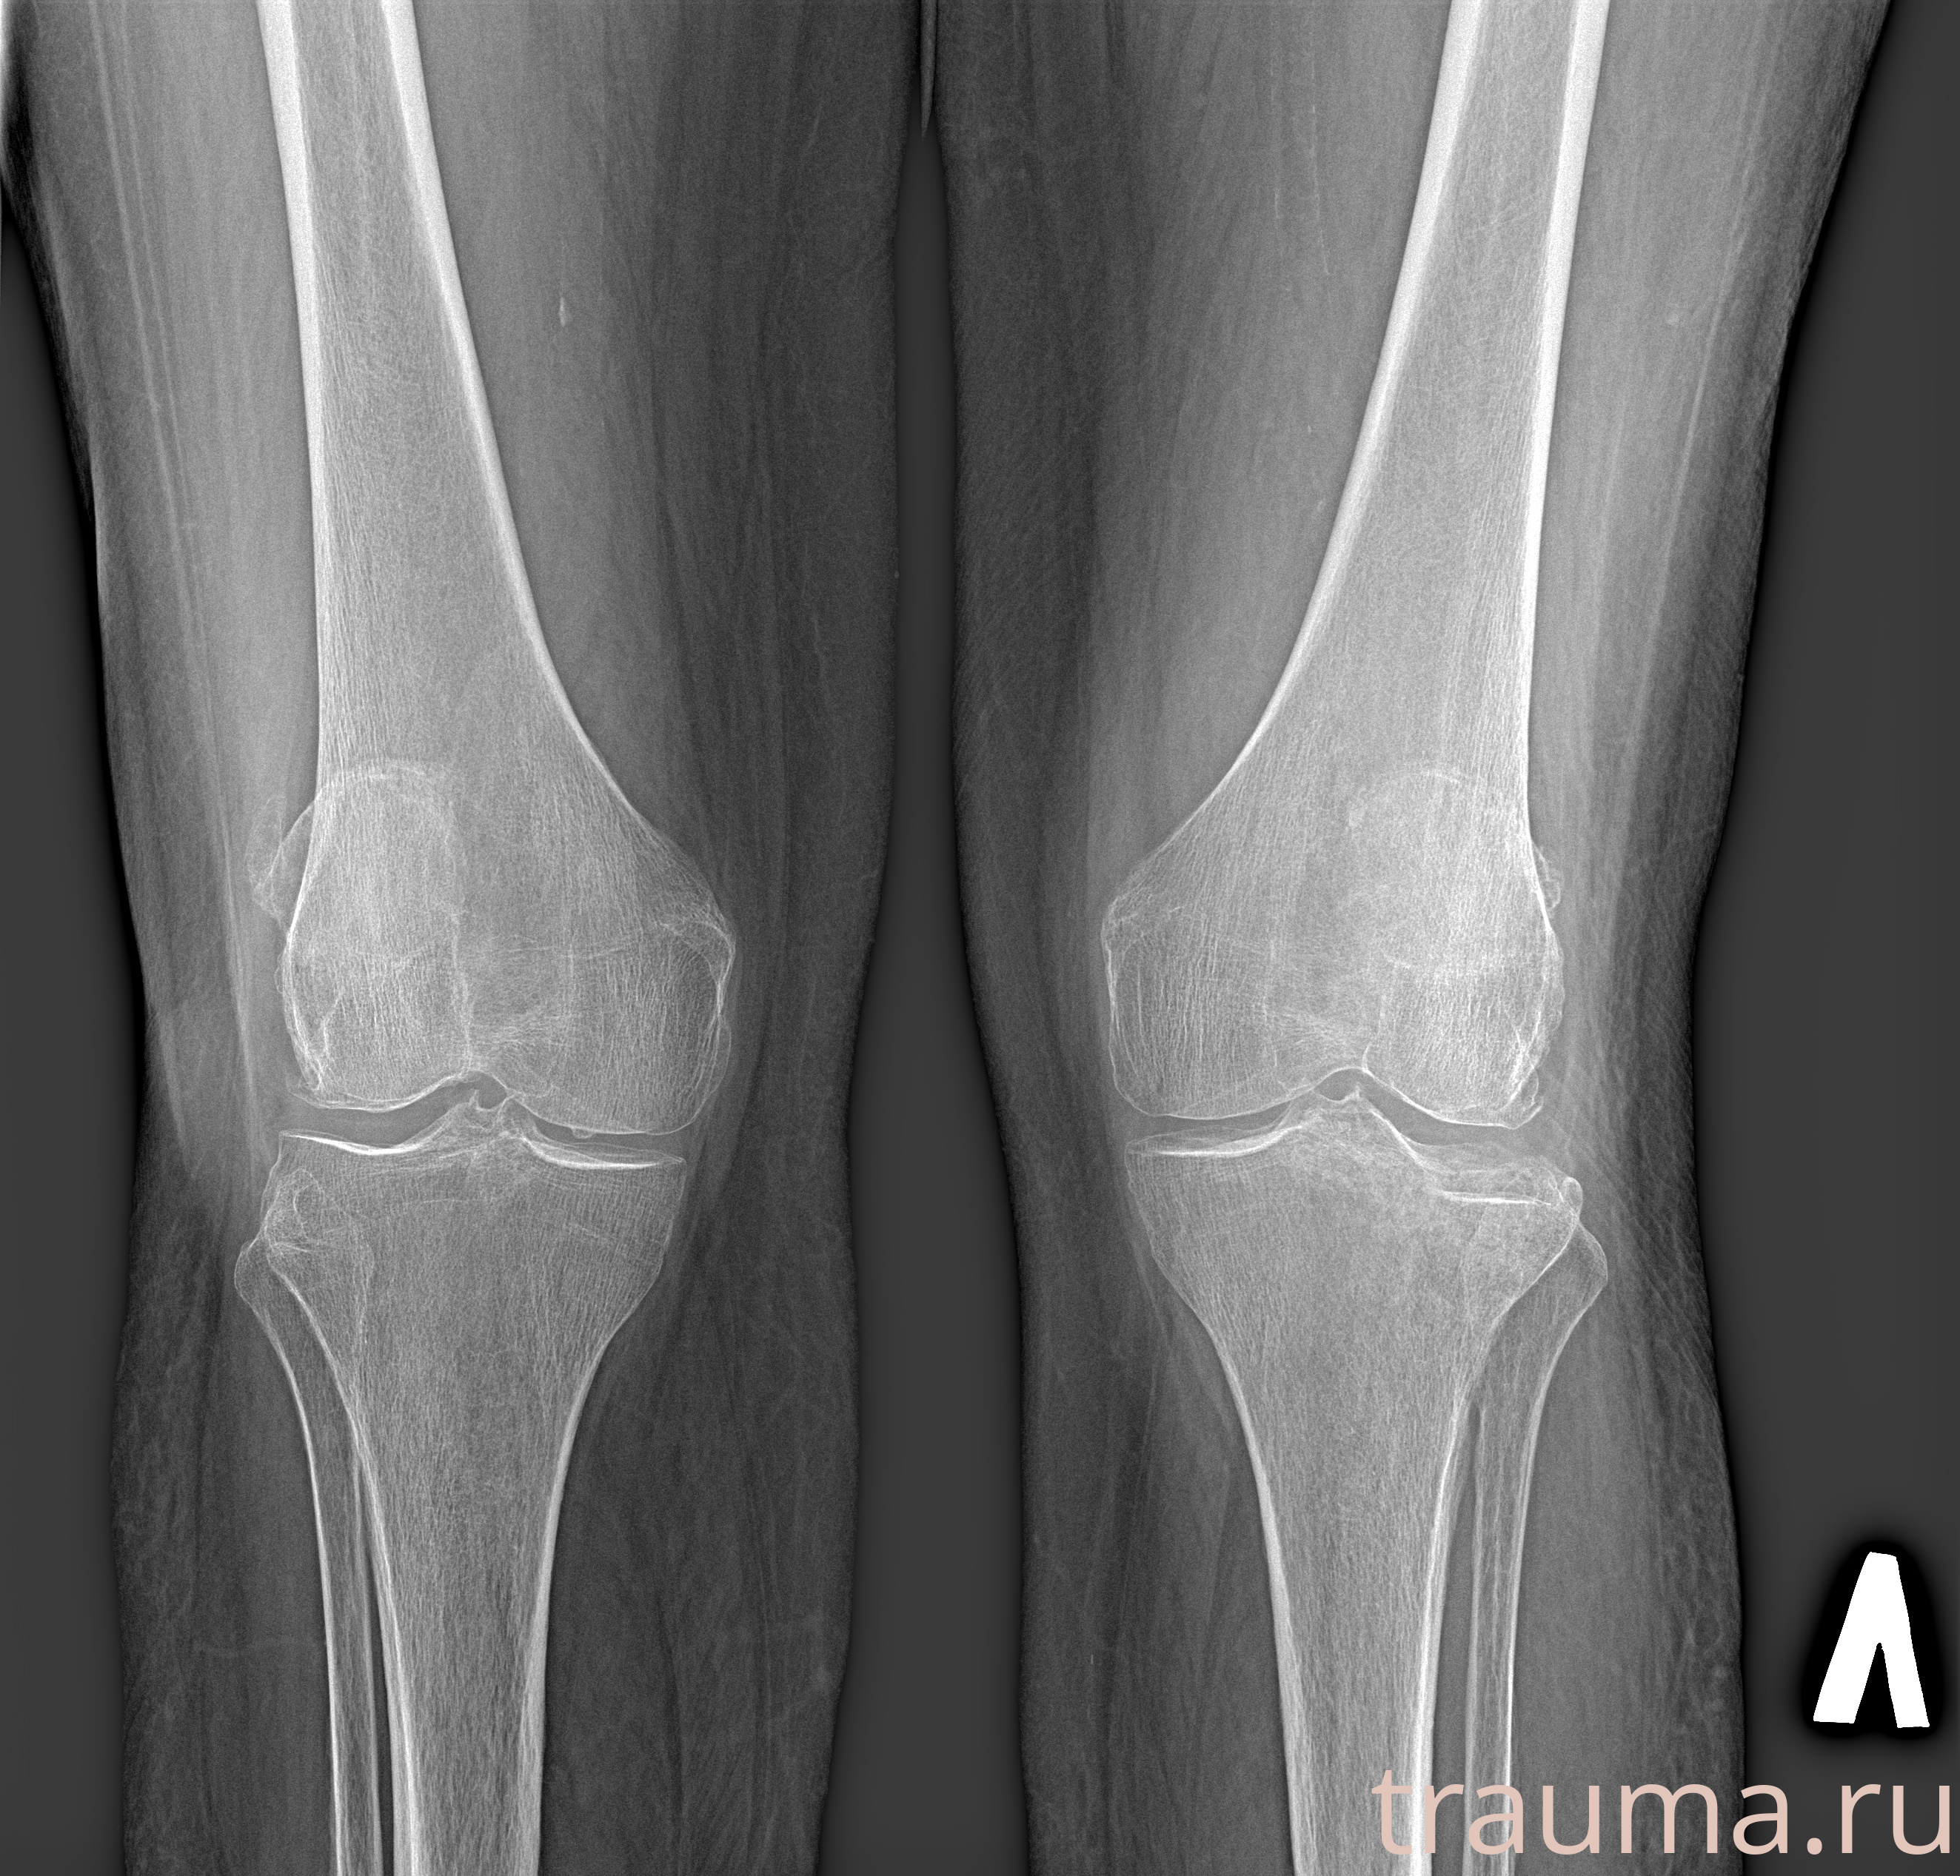

Рентгенограммы